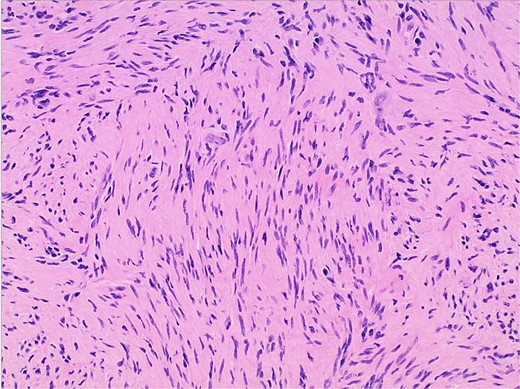

Gross examination and cut sections revealed fragments of tan–white to tan–yellow tissue with some areas of hemorrhage measuring from 1.1 to 3.6 cm in the greatest dimension. Histopathological examination of the excised mass confirmed the diagnosis of a retroperitoneal schwannoma, characterized by S100 positivity (Fig. 3) and degenerative changes, including hemorrhage, hemosiderin, and cystic degeneration (Fig. 4), nuclear atypia (Fig. 5), and perivascular hyalinization (Fig. 6).

Photomicrograph of diagnostic histopathology showing thickened blood vessel walls with hyalinization.